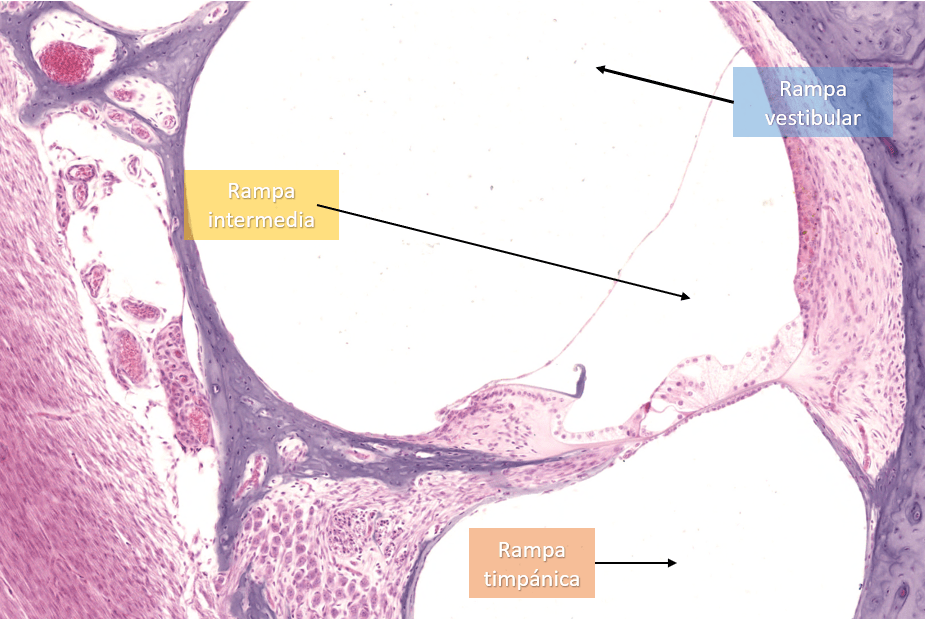

CONDUCTO COCLEAR

Identifique las rampas y las membranas a lo largo del conducto coclear.

Identifique las membranas a lo largo del conducto coclear.

Identifique las rampas a lo largo del conducto coclear.